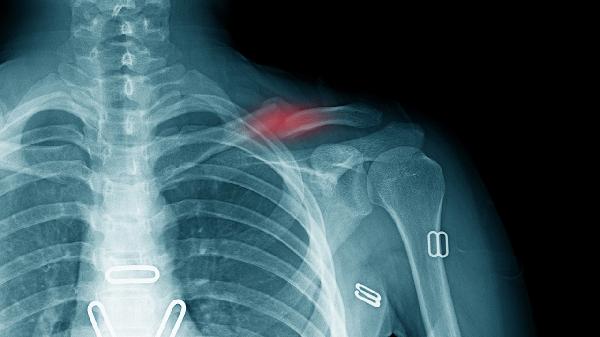

骨折恢复期每日保证500ml牛奶或等效钙摄入,阳光照射20分钟促进维生素D合成。避免吸烟饮酒影响骨骼愈合,睡眠时用枕头垫高患肢改善静脉回流。若抽搐伴随持续性疼痛或感觉异常,需及时复查X线排除内固定物移位或神经卡压。康复训练应遵循无痛原则,逐步增加踝关节活动度至受伤前水平。